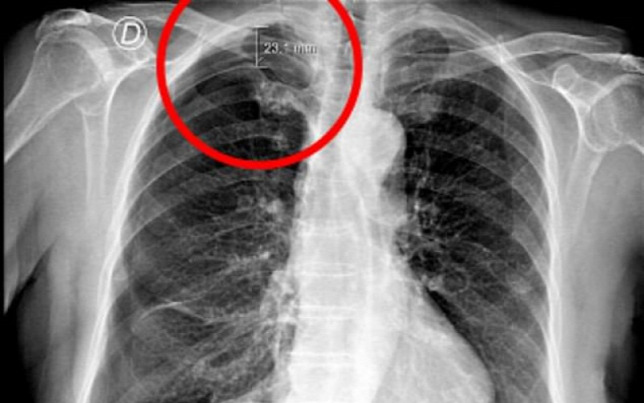

A terápiát követően a nőnek légzési nehézségei támadtak ezért orvoshoz fordult. A röntgenfelvétel hamar feltárta a probléma gyökerét: jobb tüdejének egy része összeomlott, légmell alakult ki nála.

A nő esetében az okozott bajt, hogy a tűt túl mélyen, és rossz szögben szúrták be a lapockák közötti területen. Ez azért különösen érzékeny régió, mert a tüdő csupán 1-2 centire helyezkedik el a bőr felső rétegétől, könnyű tehát kárt okozni benne.